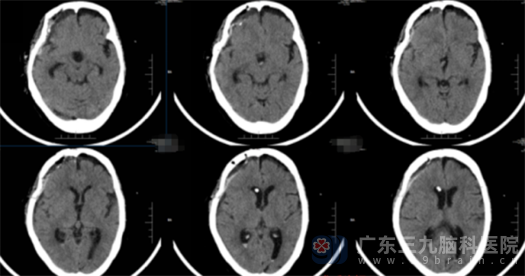

我院副院长鲁明接诊了患者,急诊完善头颅CT检查,结果提示患者鞍区占位、右侧侧脑室脑积水。此时患者已经进入昏迷状态,鲁明迅速组织神经外五科进行讨论,一致同意急诊为患者行右侧脑室外引流术。术后,患者神志清醒,症状明显好转。

术后CT